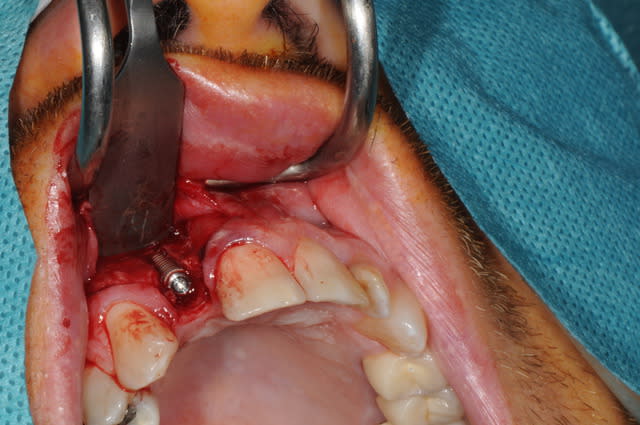

Salut, voila les photos de la chirurgie. rien d'extraordinaire , mais si certains ont des conseils, je suis preneur, j'ai la même chose à faire samedi matin

Pourriez vous me dire ce que vous utilisez pour éroder le mur palatin et éviter un axe trop vestibulaire?